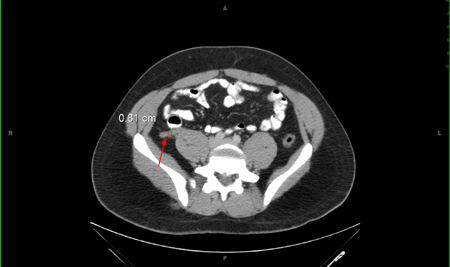

[Figure caption and citation for the preceding image starts]: Tomografia computadorizada do abdome - apêndice espessadoNasim Ahmed, MBBS, FACS; usado com permissão [Citation ends].Tomografia computadorizada do abdome - apêndice espessado​​​

apêndice anormal (diâmetro >6 mm) identificado ou apendicolito calcificado observado em associação com inflamação periapendicial